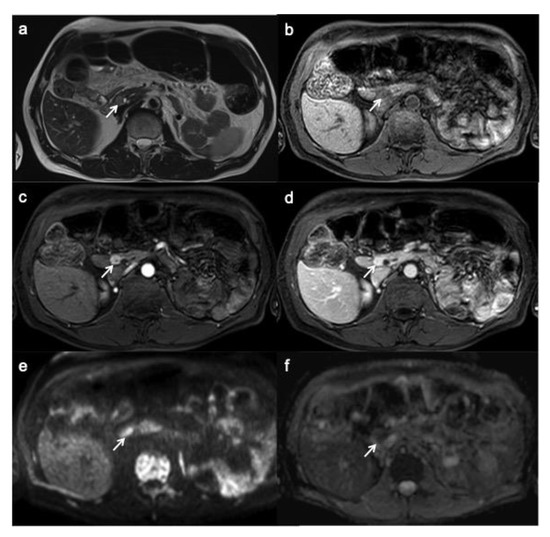

PanNEN appears, on MRI, as a T1 hypo-isointense lesion within the surrounding hyperintense pancreatic parenchyma, T2 hyperintense or less hypointense and, similarly to CT, hyperenhance during arterial phase with a slow washout (Figure 4) [25]; type of enhancement depends on necrotic and hemorrhagic changes.

Figure 4.

Small functioning pancreatic neuroendocrine tumor. T2-weighted MR image (a) shows a small lesion with well-circumscribed margin and high signal intensity (arrow). On T1W image, the lesion appears hypo-intense within the surrounding hyperintense pancreatic parenchyma (b). On contrast enhancement sequences during the arterial (c) and portal (d) phases, the lesion shows hyper-enhancement (arrow). On DWI (e) and ADC map (f), the lesion shows a clearly restrictive pattern.